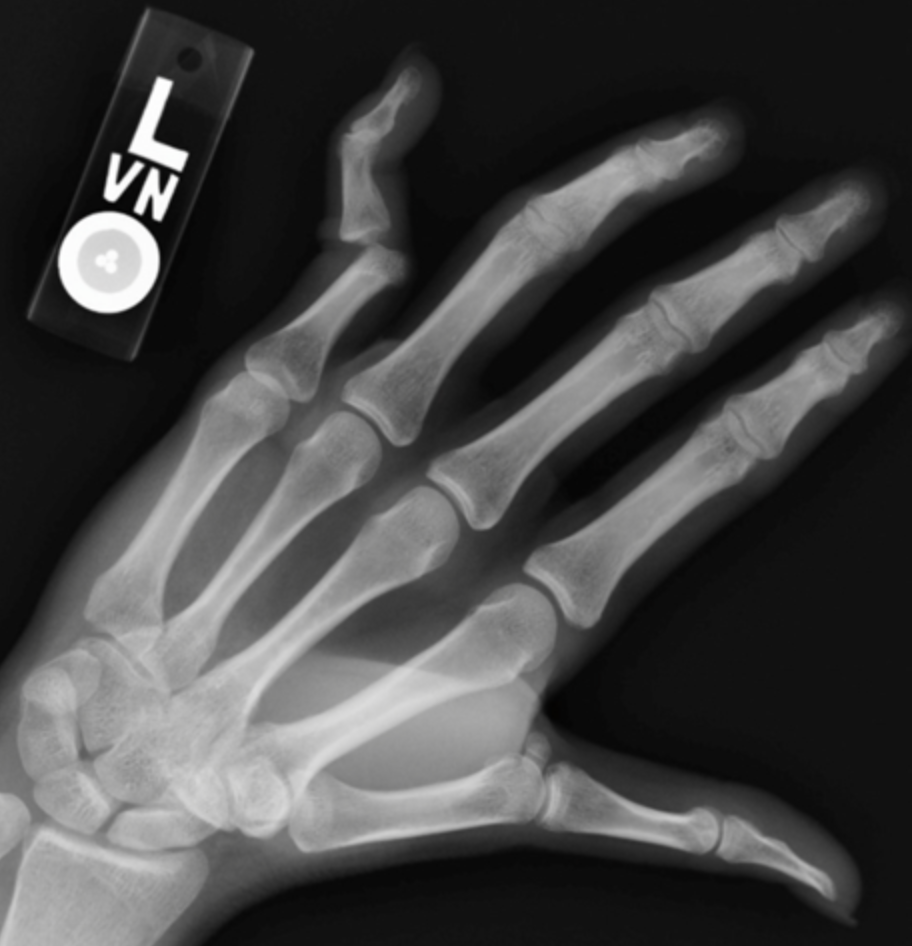

Finger Dislocations

Additional lateral dislocations

PIP dislocationPIP dislocationPIP dislocation